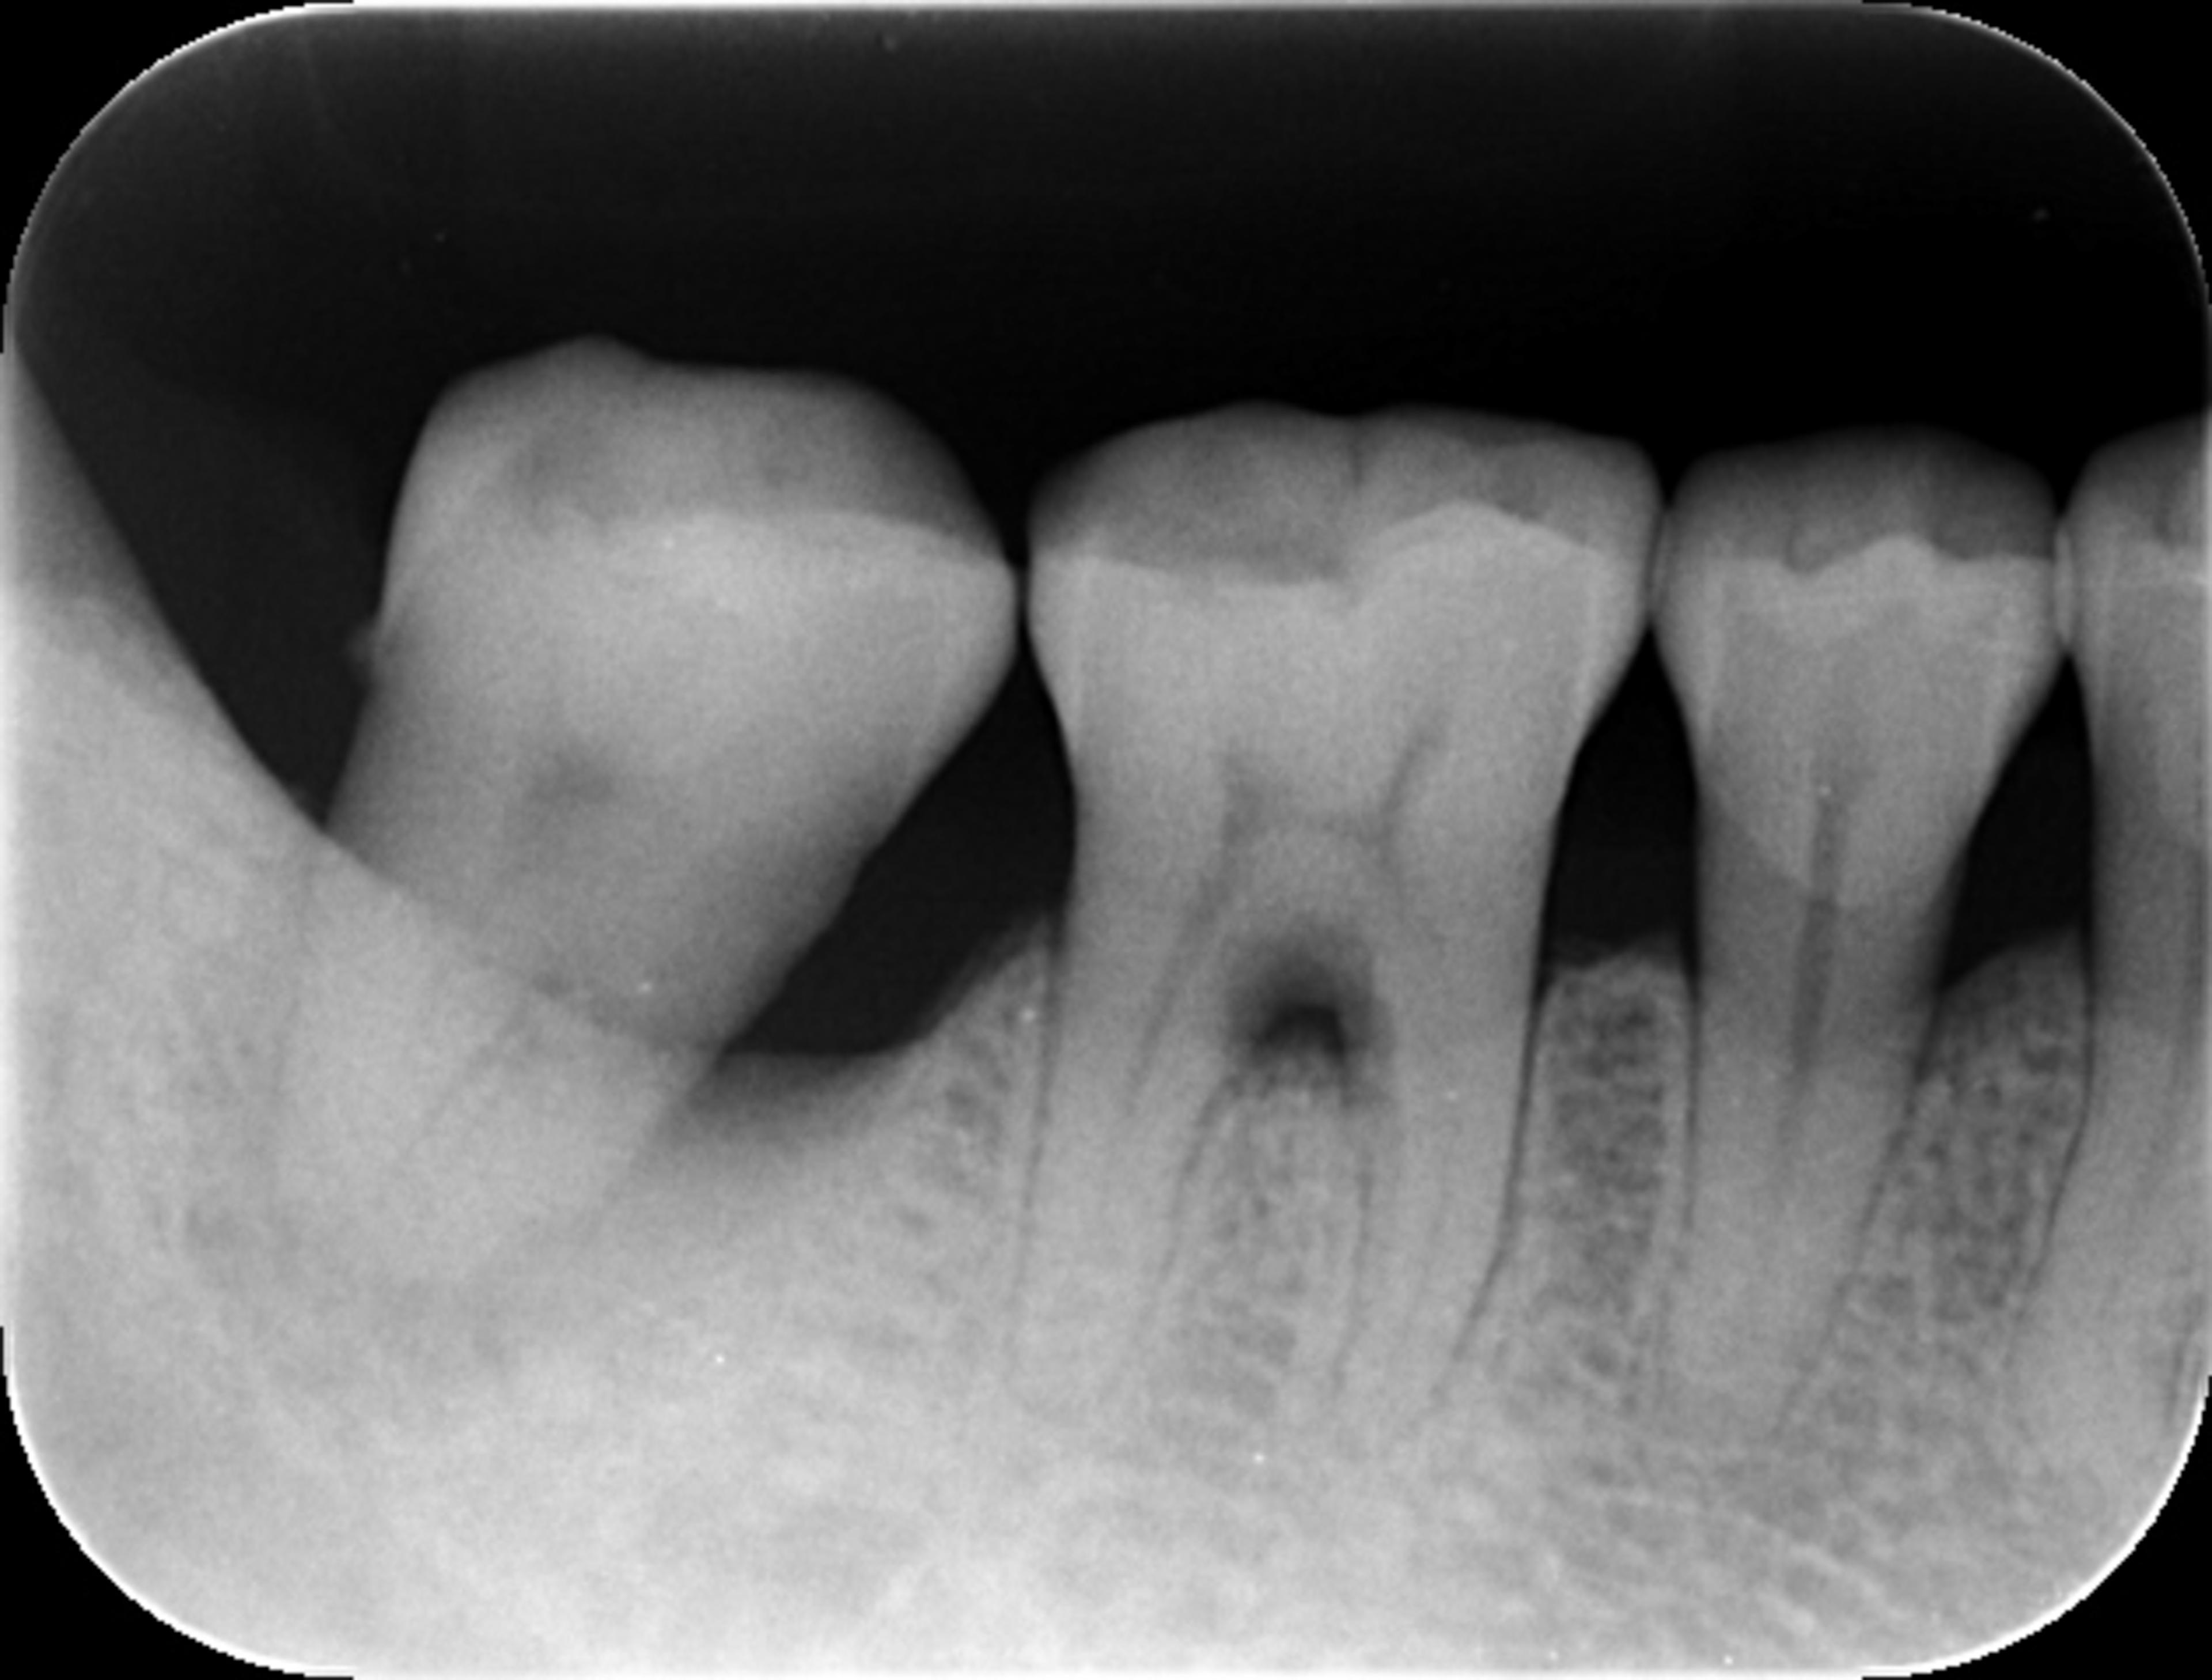

根尖を超える透過像を認める。歯を支えている骨はほとんど残っていない。

レントゲンを撮ったところ、右下の一番奥の歯に根尖を超える透過像がありました。根の下まで支える骨がなくなっているということです。ここまでの状態だとかなり厳しい状況ですが、歯の温存を強く希望されたため、チャレンジな治療になることをご説明し、納得された上で治療を進めることになりました。

根尖を超える透過像を認める。歯を支えている骨ほとんど残っていない。

広範囲にわたり付着が喪失、舌側中央、遠心のみ付着ありの状態です。噛めないほどにぐらぐらしている状態を想像してください。

ここまで限局的は歯周病が進んだ原因としては、主にはプラークコントロール、食片圧入と咬合も関与しているものと考えられます。